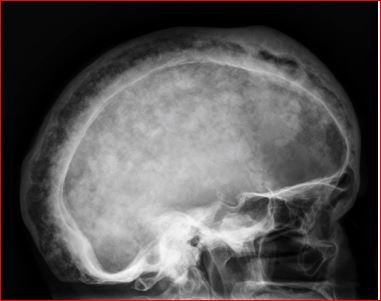

So what is renal osteodystrophy?

MORPHOLOGIC FEATURES.

The following skeletal lesions can be identified in renal osteodystrophy: